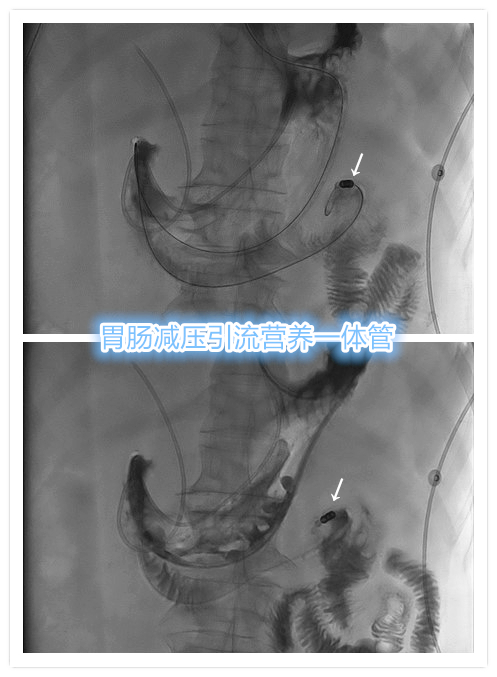

- 例2

老年女性,因胆道结石行ERCP术,术后出现急性胰腺炎及胃肠微小穿孔并发症,导致患者需要较长时间的胃肠减压引流、鼻胆管引流,及长时间肠内营养支持治疗。如采取传统置管方式,患者舒适度极差,无法耐受置管治疗。而采用胃肠减压引流营养管,可大大提升舒适度!